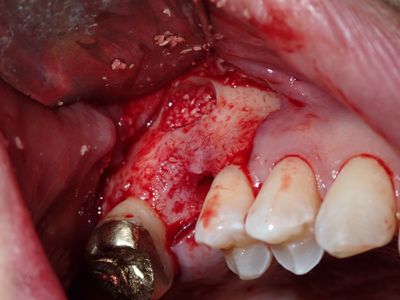

MKim - 16 - int sinus lift --> sinus aug

attempted internal sinus lift, perforation with 2.2mm drill, options: 1) abort and graft 2) place shorter and wider implant but already, palatal bone loss, limited B-L width of bone 3) sinus augmentation. proceeded with option 3, lateral window prepared with rotary and piezo instrumentation, challenging due to height and thickness of bone, no further perforation of membrane, collatape placed against membrane, bone placed in window, good pushback, implant placed.